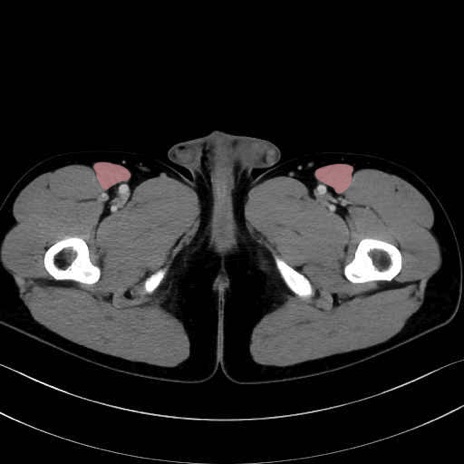

縫工筋(sartorius muscle) のCT画像の解剖

5. 大腿前面(大腿四頭筋群・伸筋群)

縫工筋 (Sartorius)

大腿直筋 (Rectus femoris)

外側広筋 (Vastus lateralis)

中間広筋 (Vastus intermedius)

6. 大腿内側(内転筋群)

恥骨筋 (Pectineus)